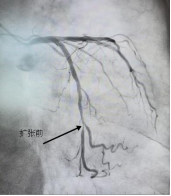

一位91岁高龄的老人,因四个多月来反复出现胸痛、心慌,最近一周症状再次加重,并伴有明显的食欲减退、吃不下饭,被送入pilipili 治疗。造影显示LCX(回旋支)远段狭窄90%,OM2开口及近段狭窄40%,随时有急性心梗的风险。李绍波主任运用IVUS(血管内超声)技术对病变血管进行检查,从传统“造影看轮廓”升级为“超声看结构”,清晰发现患者狭窄处病变以纤维斑块为主,且病变范围相对局限,符合药物球囊治疗指征。随后,李绍波主任为患者实施IVUS指导下的药物球囊治疗,术后患者血管恢复通畅,胸痛症状即刻缓解,同样无需植入支架。